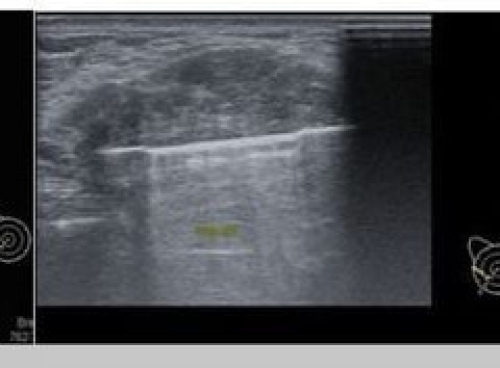

16 tháng 08, 2025Sinh thiết vú – Quy trình, các phương pháp và tại sao “sinh thiết tối thiểu xâm lấn” rất quan trọng?Xem thêm